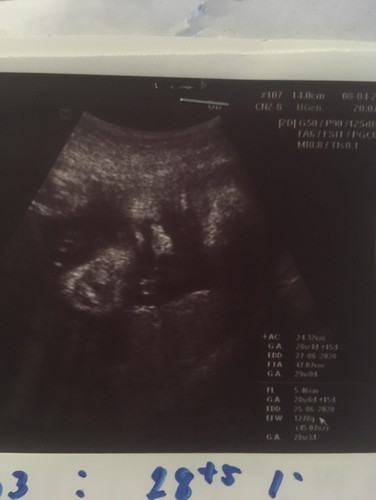

ช่วยดูหน่อยคับ ผมดูเพศไม่เป็น

ลูกชาย รึ ลูกสาว คับ ดูไม่ออกเลย

คุณหมอว่ายังไงบ้างคะ :)